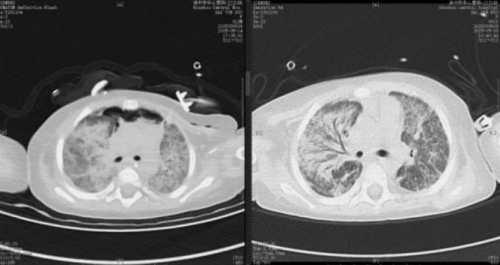

3.并发症识别与处理:5 月 28 日复查 CT 显示双肺炎症较 5 月 14 日明显吸收,印证治疗有效(见图3)。但同期发现双肾结石或钙化灶,经评估后考虑与药物等因素相关,无急性梗阻,遂采取补液利尿保守治疗(见图4)。

图 3